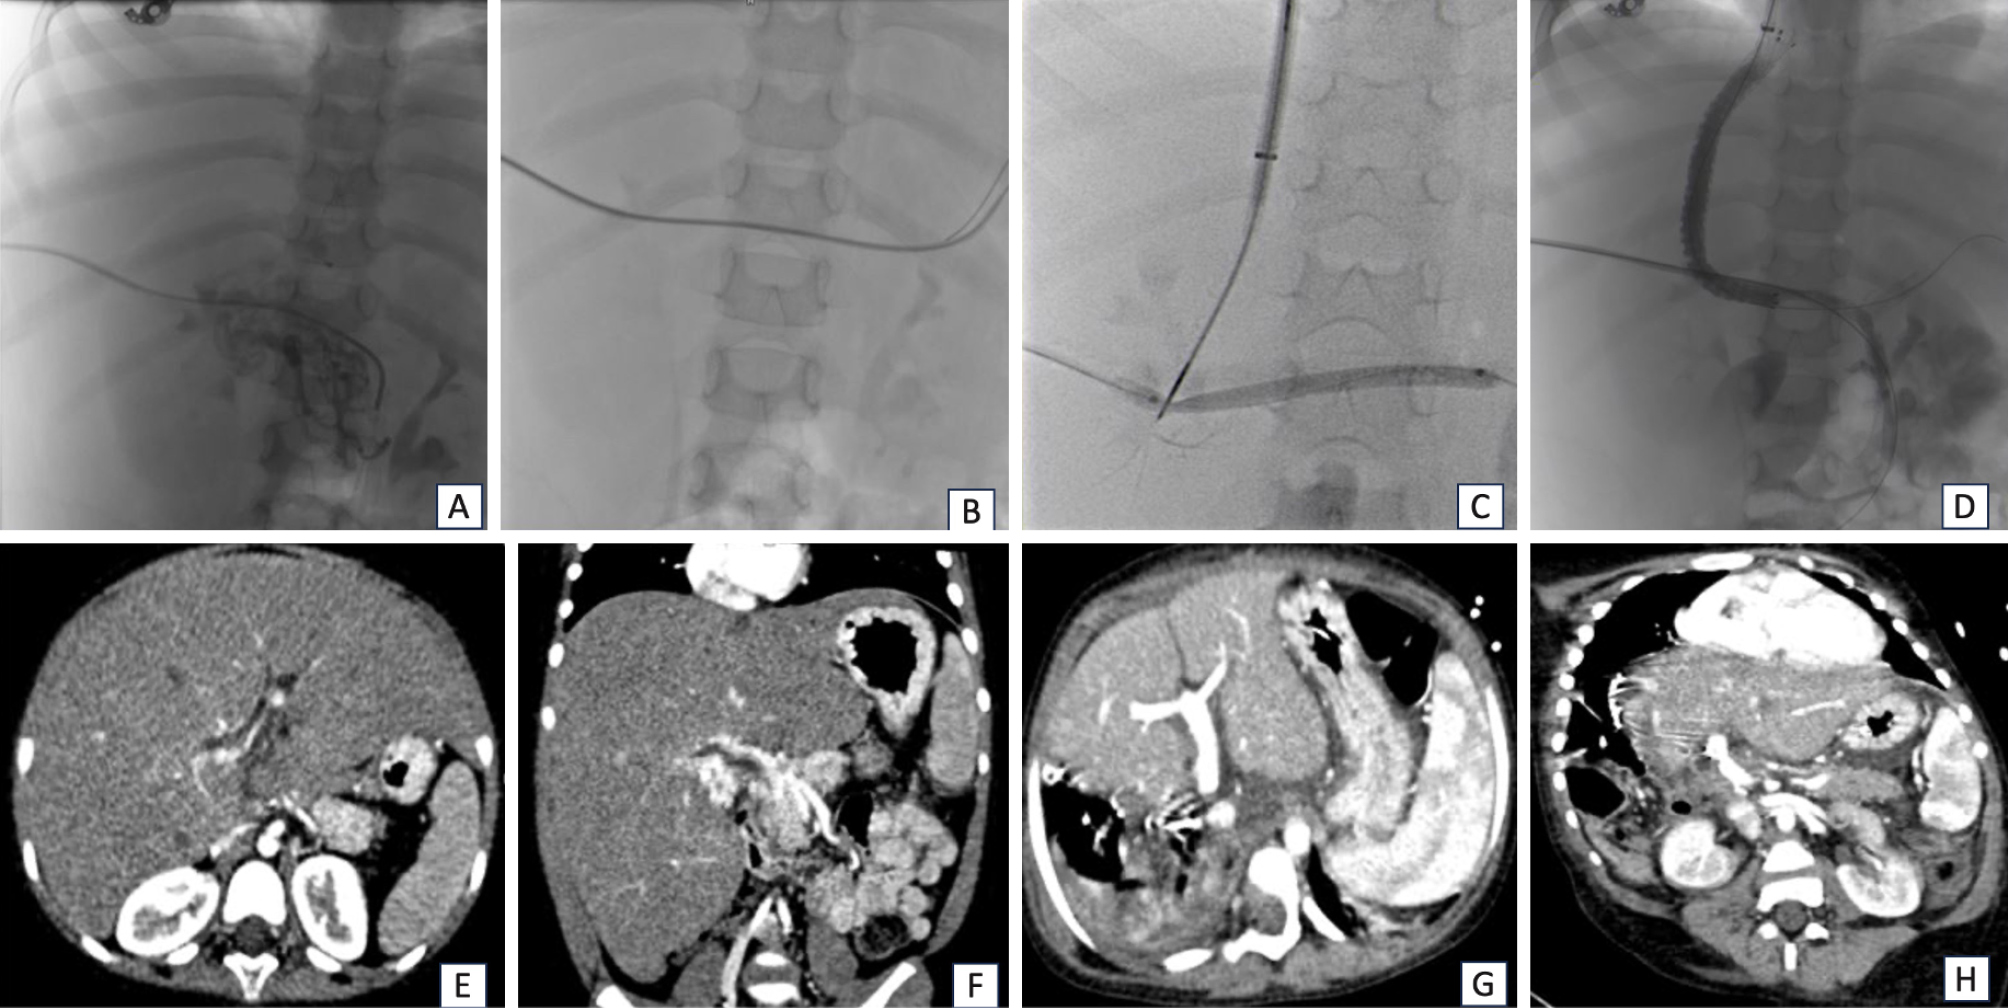

- 3A Review of Treatment for Type II Endoleak after Endovascular Abdominal Aortic Aneurysm RepairHiroki Horinouchi